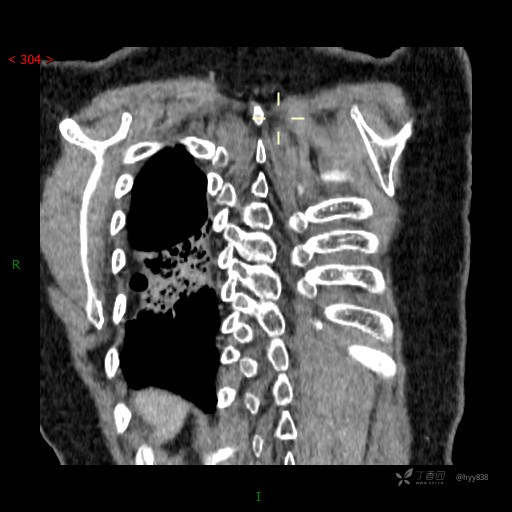

静脉期